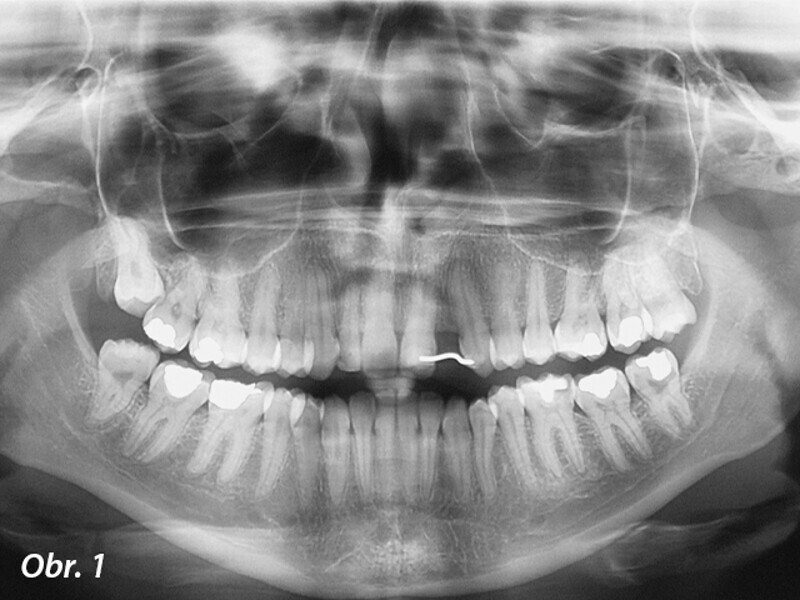

Aproximální rozšíření mezi kořeny zubů za účelem zavedení úzkého implantátu